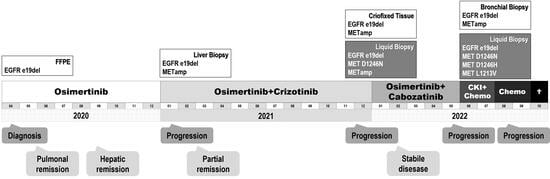

2. Case Presentation